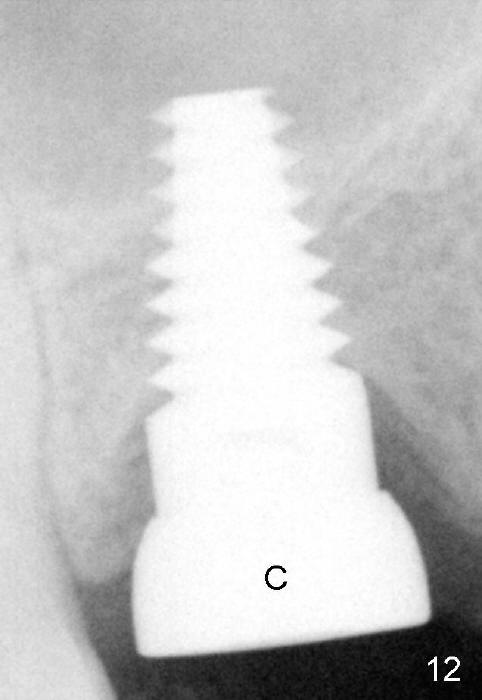

Following local anesthesia, the failing implant is removed without resistance. The sinus floor is present. The lateral walls are intact, although probably short. A series of rounded tapered osteotomes (2-5 mm in diameter) are used for sinus lift at the depth of 14 mm. A 4.5x14 mm tap is inserted (Fig.10). One more carpule of Lidocaine is administered. A 6x14 mm implant is placed with torque more than 60 Ncm without additional bone graft (Fig.11). A 6-month postop PA confirms osteointegration (Fig.12). An abutment is placed (Fig.13) for a definitive crown (Fig.14). PA taken 6 months post cementation shows that bone density mesial to the implant increases (Fig.15 <).